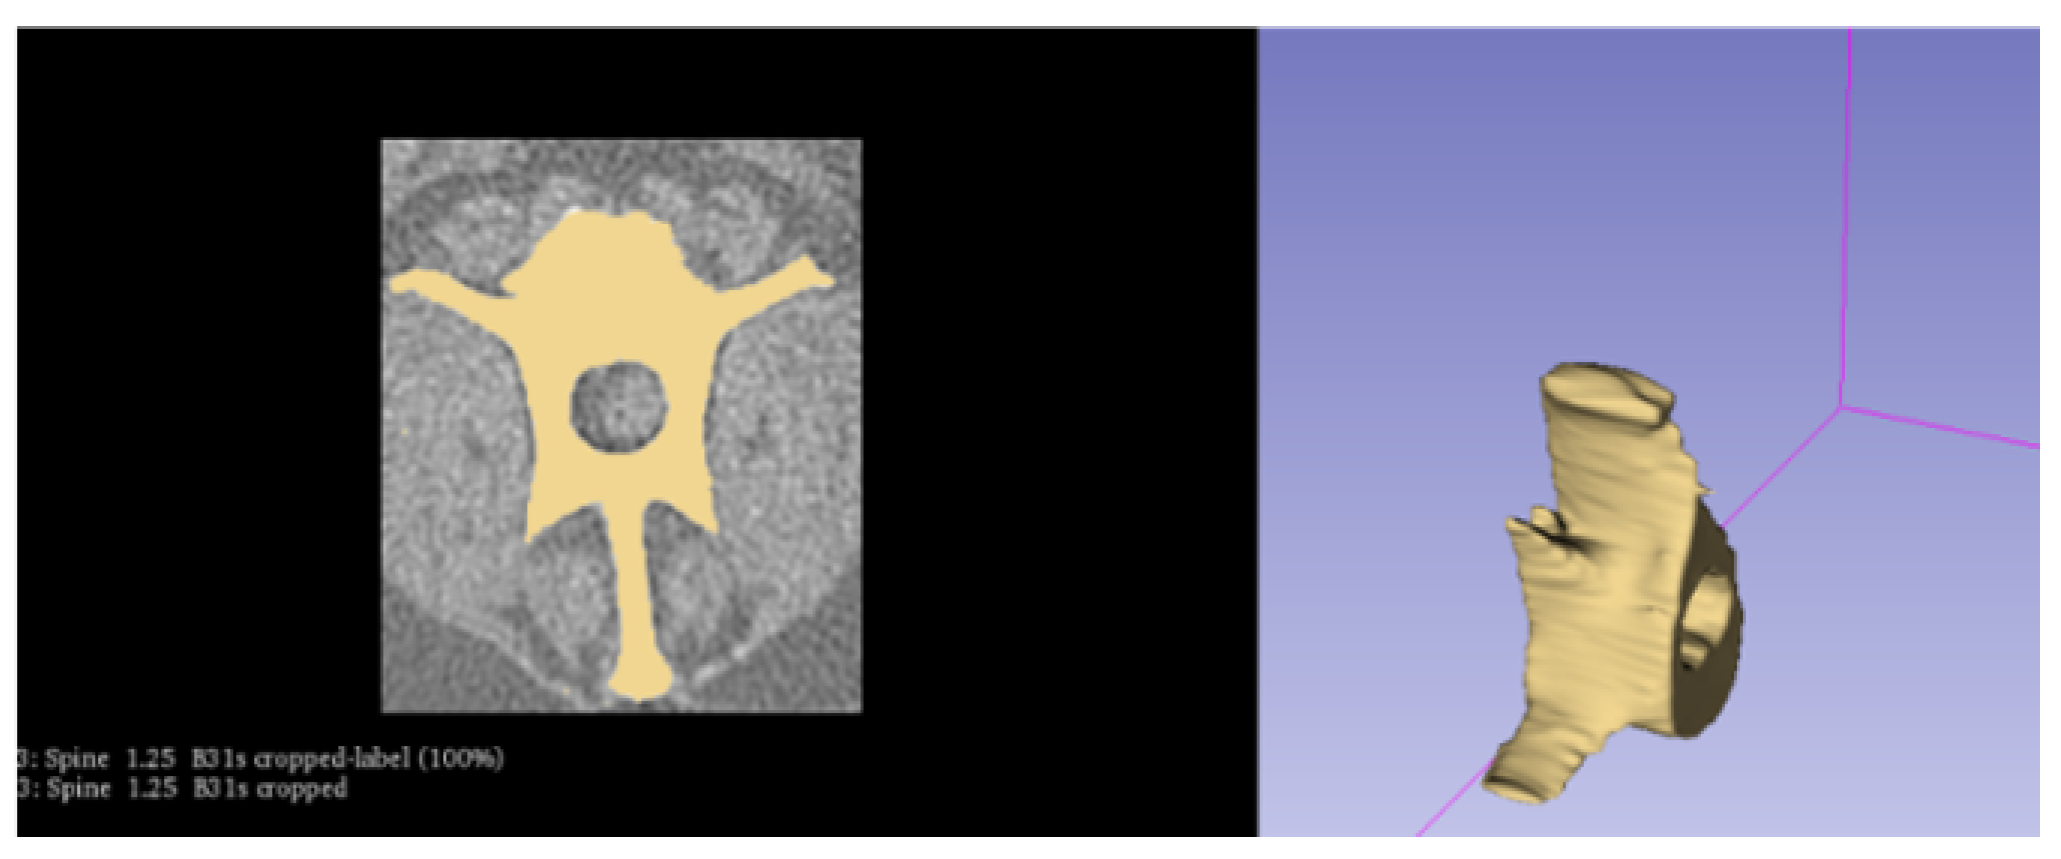

2.2. Creating the Geometry

- Fedorov, A.; Beichel, R.; Kalpathy-Cramer, J.; Finet, J.; Fillion-Robin, J.C.; Pujol, S.; Bauer, C.; Jennings, D.; Fennessy, F.; Sonka, M.; et al. 3D Slicer as an image computing platform for the Quantitative Imaging Network. Magn. Reson. Imaging 2012, 30, 1323–1341. [Google Scholar] [CrossRef]